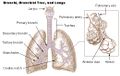

الحنجرة (بالإنجليزية : Larynx) هي الجزء الأمامي من العنق, عريضة من أعلى, مثلثة الشكل, وتتكون من عدة غضاريف تتحرك بوساطة عضلات مبطنة بغشاء مخاطي, يمتد في تجويفها الحبلان الصوتيان, حيث ينتج الصوت عن طريق الهواء المدفوع من الرئتين ليذبذب الأحبال الصوتية. ويحرس مدخل الحنجرة زائدة غضروفية تسمى لسان المزمار, له دور مع حركة الحنجرة عند الإبتلاع.